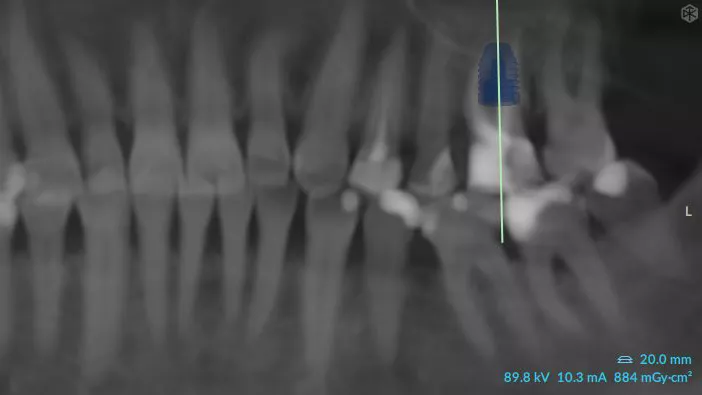

3a. 3b. 3c. 3D volumetric diagnosis and planning of implant therapy.

3a

3b

3c

4. Radiograph exhibiting a suitable septum for immediate implant placement.

4